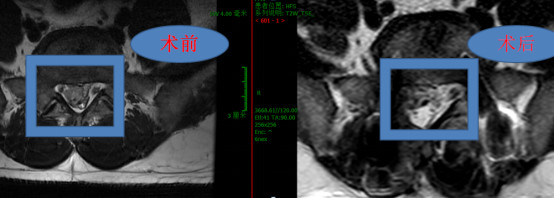

术后复查磁共振显示:脱出髓核被彻底拿干净,硬膜囊膨隆,硬膜外间隙清晰可见。